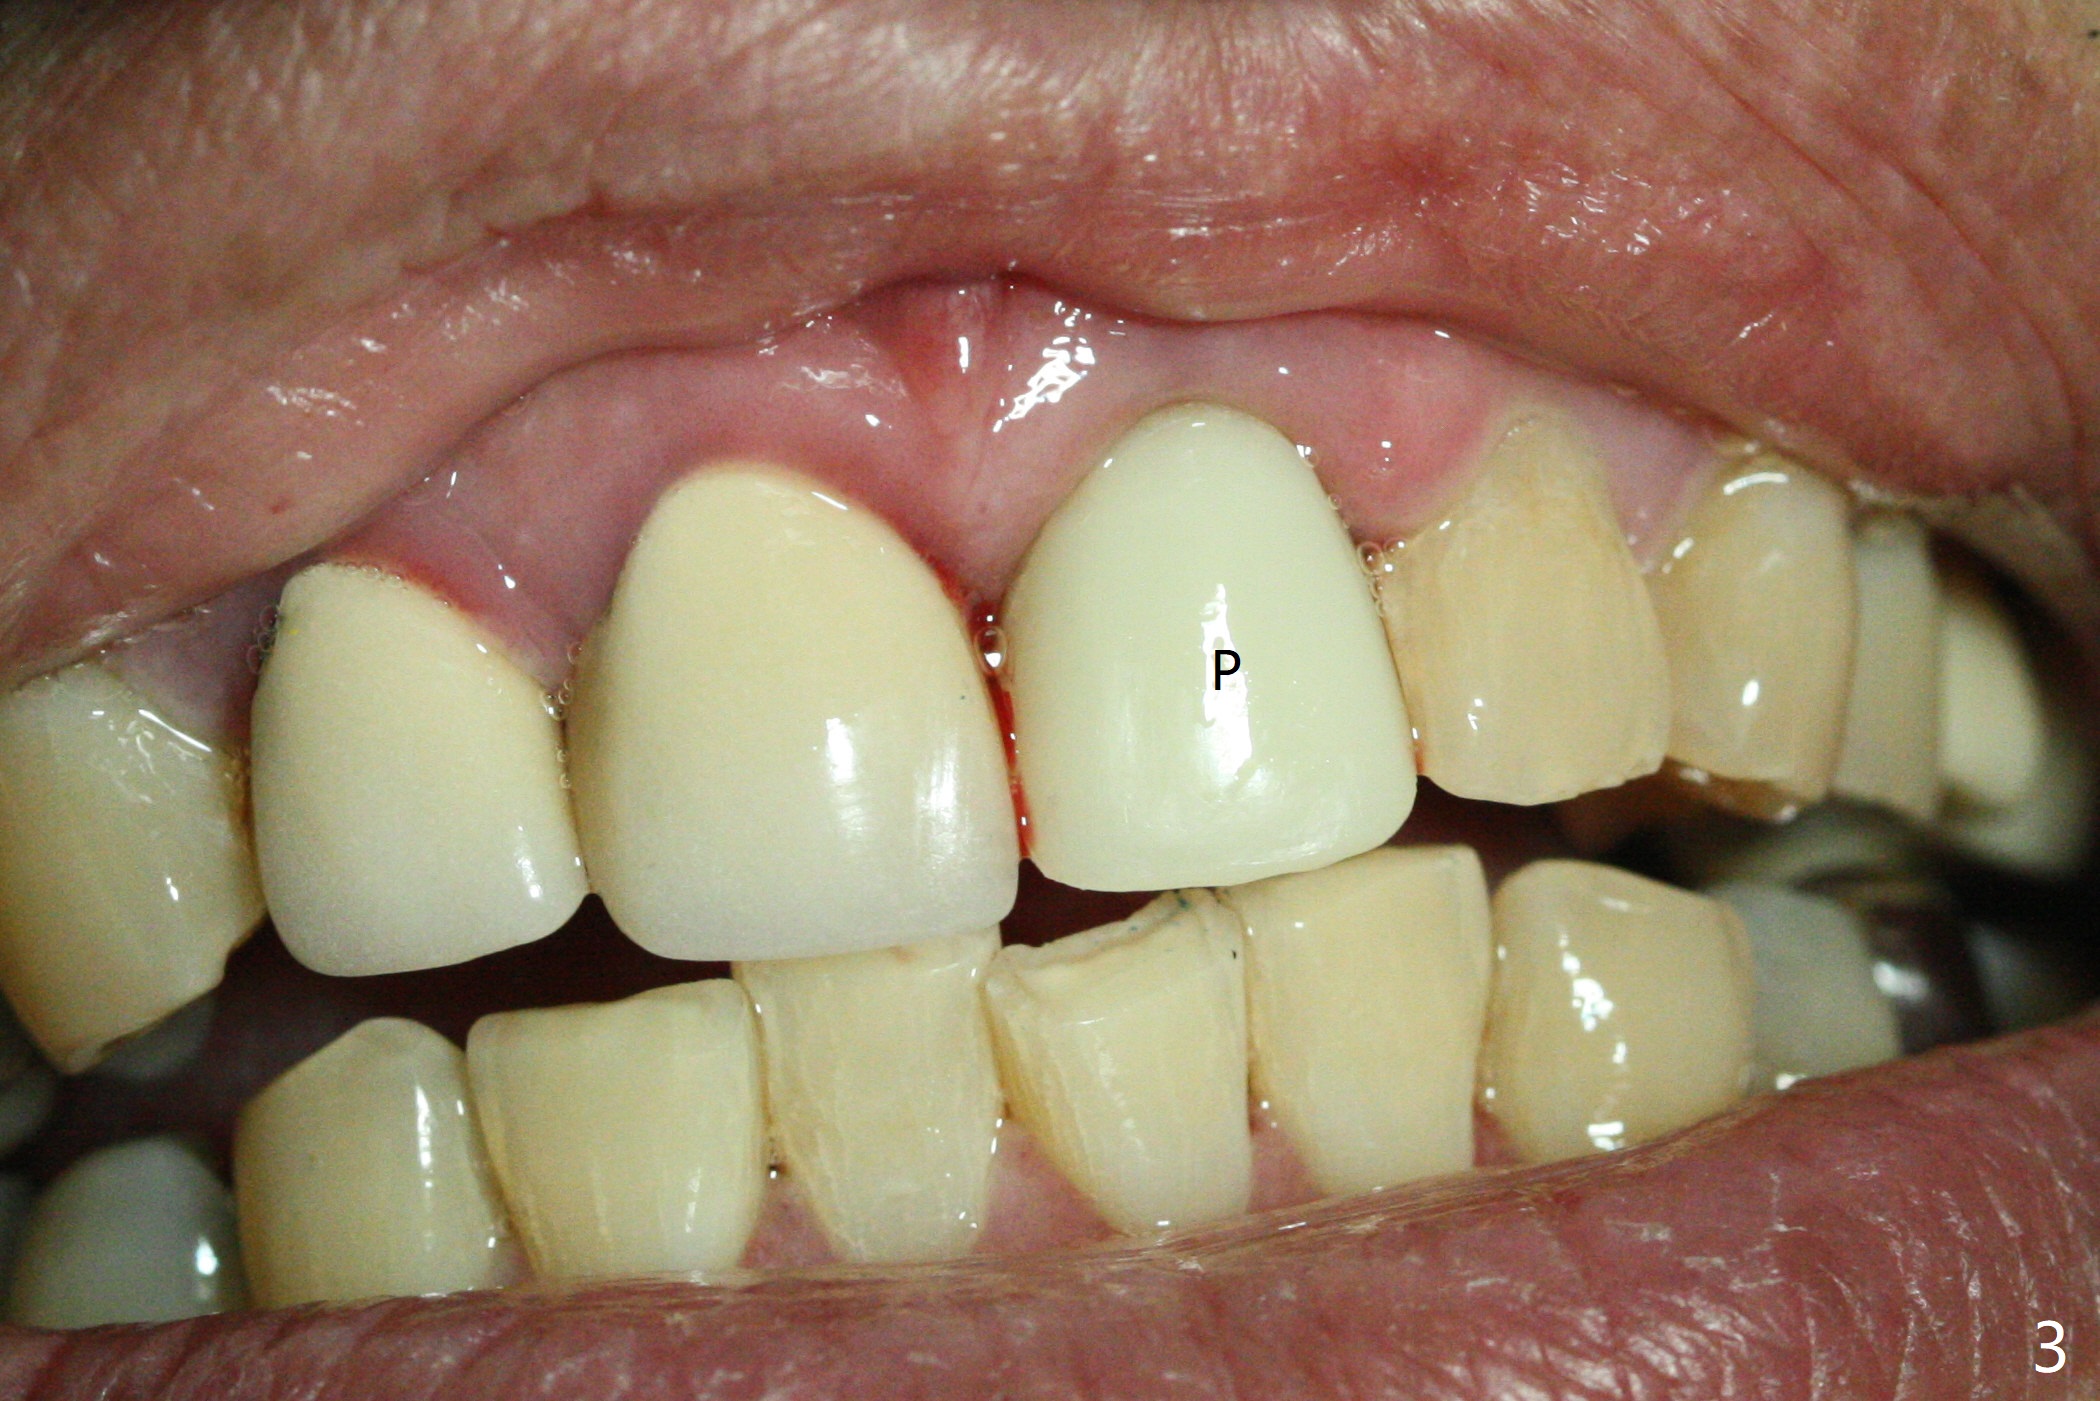

The buccal plate at #9 remains intact in spite of difficult extraction. Osteotomy is initiated in the palatal slope of the socket (Fig.1). The latter looks large when osteotomy is finished for a 3.8 mm implant. Without further osteotomy, a 4.5x14 mm SM implant is placed with primary stability (Fig.2). Without much attention, the coronal end of the bone-level implant is gradually deviated buccal, although the buccal gap is still 2 mm. An angled abutment is used (Fig.2); the future access hole is also buccal. Screw retention is impossible for cosmetic reason (Fig.3). To keep the access incisal and palatal, keep removing palatal bone sequentially. Or start osteotomy in the mid point of the palatal slope and keep the coronal end of the trajectory (Fig.5 pink line) palatal to the imagined incisal edge (Fig.4 white outline). The implant should be small (3.5 mm instead of 4.5 mm) so that it is easy to change the trajectory. The bone graft seems to have disappeared 3.5 months postop; the implant appears to have not been placed deep enough (Fig.6). In fact the implant plateau is < 2 mm subgingival palatal. An anterior immediate implant should be placed deep to reduce periimplantitis. There is reduced risk associated with abutment screw loosening, as compared to the posterior. Luckily the patient has used water pik since implant placement. On the other hand, water pik may be related to loss of bone graft. Therefore, water pik should be used 1 month post bone graft associated with immediate implant. The bone graft remains around the abutment cuff 4 months postop (Fig.7; immediately post cementation).